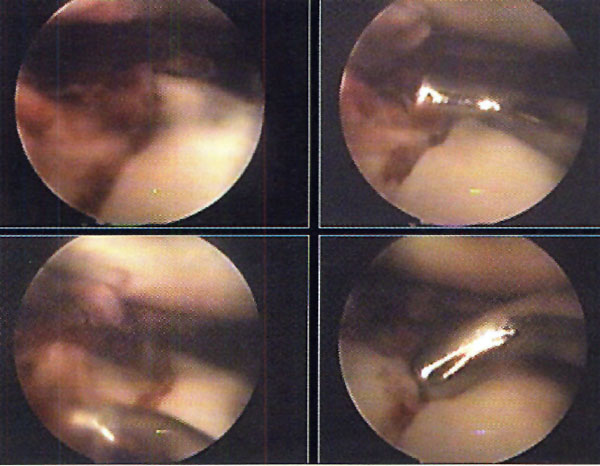

En el caso de las fracturas por cizallamiento, realizamos un abordaje longitudinal sobre el platillo afectado (evitando la apertura de la cápsula articular y la desinserción meniscal), a través del cual desimpactamos y elevamos los fragmentos cizallados. Simultáneamente y mediante un escoplo laminar o escoplo gubia, desimpactamos los fragmentos fracturarios articulares bajo visión artroscópica, colaborando en las maniobras de reducción. (Foto 7) Posteriormente realizamos la osteosíntesis, la cual dependerá de las características de la fractura que estemos tratando. Si utilizamos tomillos canulados con arandela, la colocación es percutánea próxima a la línea articular, para que actúen de sostén, protegiendo el hundimiento de los fragmentos (fracturas tipo III), o realicen compresión del fragmento cizallado (algunas fracturas tipo I y II.) La placa con tornillos es utilizada en aquellas fracturas con componente de cizallamiento, con importante conminución, desplazamiento u osteopenia de sus fragmentos.

Foto 7: Reducción con escoplo